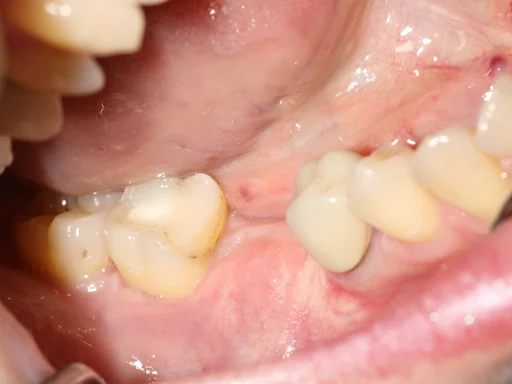

Patientenfall - Implantologie - Zahn 46 - 4

Schritt 4

Die Kosten für den chirurgischen Teil der Direktimplantation betrugen 2449 €. Der prothetischen Teil kostete 2260,- €.